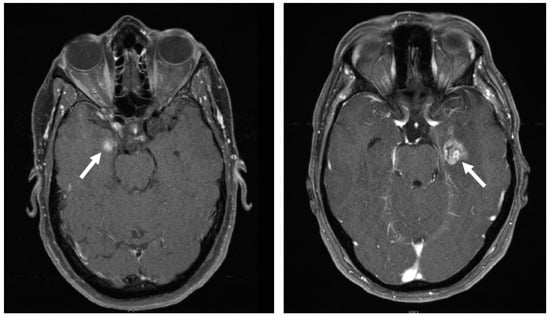

2.2. Differentiation between Radiation Reaction and Radiation Necrosis

The differentiation between temporal lobe reactions and necrosis can be challenging, particularly because the former often transitions fluidly into the latter (Figure 1). A board-certified radiologist with extensive experience with skull base tumors assessed all follow-up MRI scans. Distinction between BBB disorders (temporal lobe reactions) and radiation necrosis were made using the most recent MRI with contrast enhanced T1-sequence, T2-sequence, SWI-sequence, previous MRI, development over the course of time, and, if available, other modalities of radiologic examination.

Figure 1. The arrows point to examples for temporal lobe reaction (left) and necrosis (right).